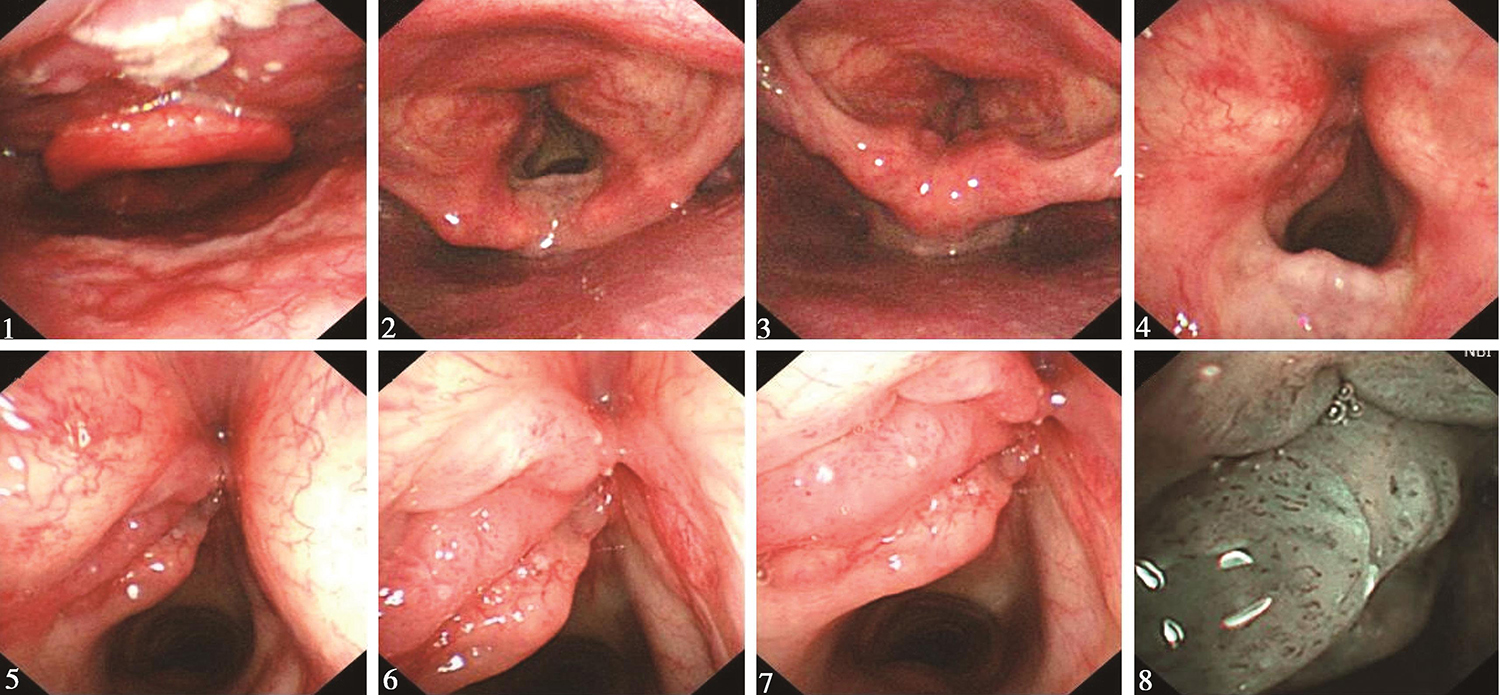

1.2015年6月11日电子鼻咽喉镜检查

鼻腔进镜顺利。鼻咽部结构完整,黏膜光滑,未见明显异常。口咽双侧扁桃体未见肿大。舌根部淋巴滤泡增生明显。下咽部表面光滑,双侧梨状窝对称,未见明显异常。喉部会厌及双侧披裂结构正常,黏膜光滑。声门区左侧声带可见粗糙不平肿物生长,左侧声带明显增厚,累及全长,向前侵及前联合,向后达声带突,向左侧喉室内生长,左侧室带前端受累及(图1)。右侧声带萎缩,表面黏膜充血,未见明显侵及。双侧声带活动未见受限。声门下未见侵及。

图1 喉镜示左侧声带肿物

内镜诊断:

声门型喉癌,已有病理。